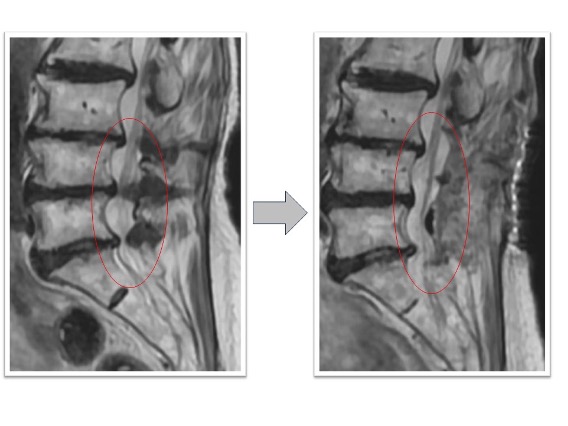

頚椎固定術実例(*患者様の許可を得て掲載しています)

頚椎症性椎間孔狭窄、椎間板ヘルニア、頚椎後湾

両上肢から肩にかけての痛み、頸部痛の患者様に対してC4/5/6の頚椎前方固定術を実施しました(赤丸)。術後には狭小化していた椎間高が回復し、さらに術前には同部位で頚椎の後弯(頚椎が後ろに凸となり頭が前に下がる状態)が認められていましたが、術後は頚椎の並び(アライメント)が改善しています。また、同時にこの断面では見えていませんが椎間孔も上下に拡張することで術後にあった肩から上腕への痛みが術後消失しています。